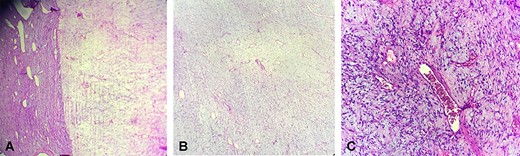

Histopathological examination appeared well demarcated and showed alternation of hyper- and hypocellular areas, with abundant blood vessels (Fig. 2a). The stroma appeared edematous. Tumor cells were spindle shaped with fine chromatin (Fig. 2b). There were no mitotic figures observed.

Microscopically, (a) showed alternation of hyper- and hypocellular areas (hematoxylin and eosin stain X10), (b) with spindle-shaped tumor cells and abundant blood vessels (hematoxylin and eosin stain X20)